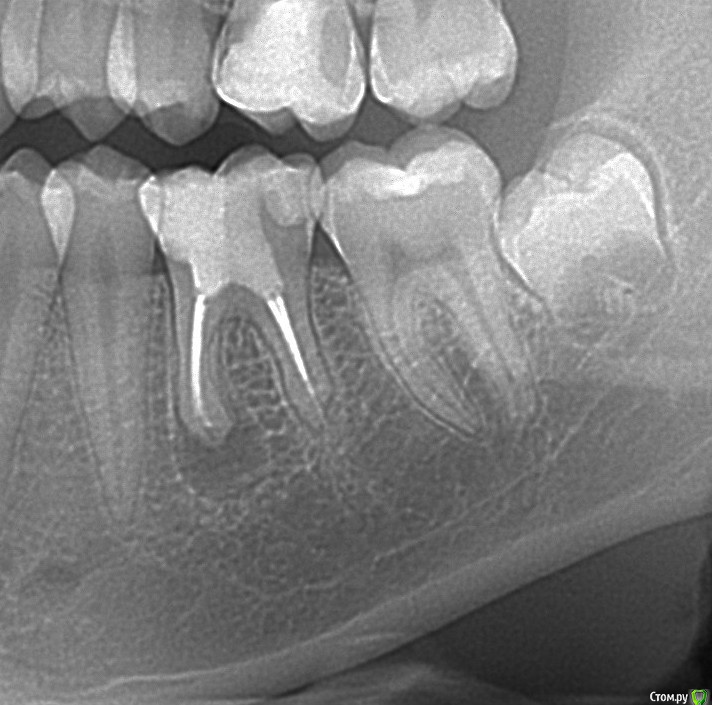

igorstom Опубликовано 10 декабря, 2016 Автор Поделиться Опубликовано 10 декабря, 2016 И вот наконец заставил сделать контрольный снимок. К сожалению далеко не всех можно пронаблюдать пациентов. Хотя есть в планах создать тему "Отдаленные результаты". Есть пациенты, которые наблюдаются более 8 лет.Вопрос. Гранулема исчезла? Или снимок просто не показывает? Раньше зуб периодически при переохлаждении или простуде всегда давал знать. Сейчас более 1,5 лет ни разу не пискнул. Об эндо чуть позже напишу. Ссылка на комментарий